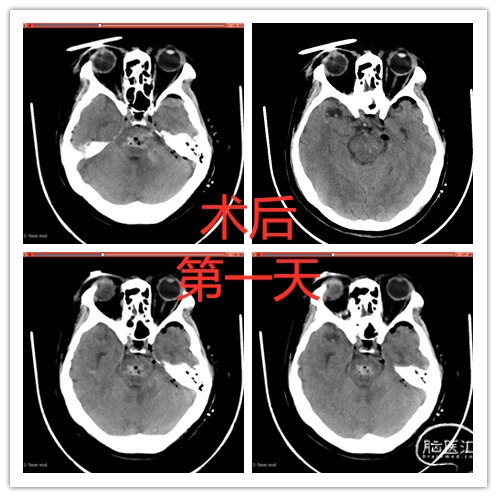

术后1周患者转醒,自主睁眼,能按吩咐活动左侧肢体,左上肢肌力3级。有轻度左侧面神经功能障碍,静息状态下闭眼完全。(详见视频)